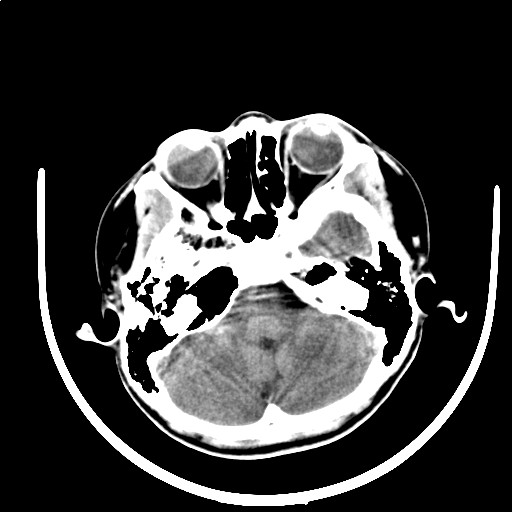

标题: PED3416:F,12Y,智力下降,学习成绩差,8个月时发过高烧。

右侧大脑发育不良伴动静脉畸形。

颅面血管瘤病(sws)。

右侧半球萎缩,软化,多量脑回样钙化,考虑颅面血管瘤病,建议dsa检查

右侧半球萎缩,软化,多量脑回样钙化,同侧颅盖板障增宽,考虑颅面血管瘤病,建议dsa检查与化脓性脑膜炎后遗改变鉴别。